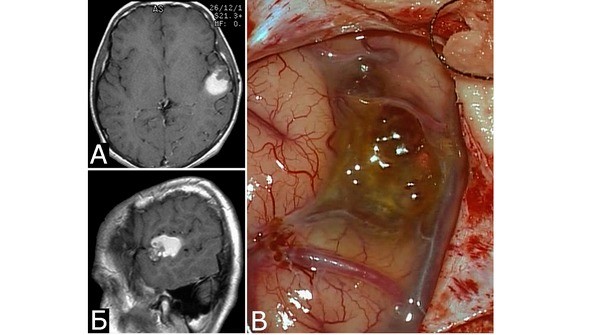

Кавернозные мальформации имеют характерный вид, который трудно спутать с каким-либо другим видом патологии. Они представляют собой округлые образования красно-синюшного или бурого цвета, с неровной, бугристой поверхностью, четко отграниченной от окружающей ткани (рис. 7).

Бугорки, образующие поверхность каверномы, представляют собой полости, заполненные кровью, которые либо плотно прилежат друг к другу, либо включены в строму каверномы в виде отдельных образований, легко отделяющихся от основного конгломерата и напоминающих горошину. Размеры венозных полостей, или «каверн», и их соотношение со стромой могут быть самыми различными. Некоторые каверномы состоят преимущественно из каверн с тонкими, быстро разрушающимися стенками. Размеры таких каверн могут быть достаточно крупными. При таком варианте строения в ходе хирургического вмешательства зачастую сложно обнаружить более или менее плотный участок, который может быть взят для гистологического исследования. Такие образования хирурги нередко характеризуют как «инкапсулированные гематомы».

Рис. 7. Вид каверномы на операции в процессе выделения (А) и после удаления единым блоком (Б)

Ткани, окружающие каверному, чаще всего грубо изменены. Типична желтая окраска мозгового вещества, мозговых оболочек или нервов, свидетельствующая о перенесенных кровоизлияниях (рис. 8). Этот признак помогает обнаружить каверному в ходе хирургического вмешательства.

В небольшом числе случаев перифокальные изменения мозговой ткани отсутствуют (рис. 9).

Рис. 8.Б-ной И-юн, 13 лет. Кавернозная мальформация и гематома оперкулярной зоны слева. Повторные кровоизлияния. А, Б – МРТ, режим Т1, аксиальная и сагиттальная проекции. 4-е сутки после 2-го кровоизлияния. Видна ткань КМ в виде гетерогенного сигнала, и гематома в виде гиперинтенсивного сигнала, расположенная кзади от КМ. В – интраоперационное фото после вскрытия ТМО, 2 месяца после 2-го кровоизлияния. Виднаи желтая окраска окружающих тканей и отдельные каверны, выходящие на поверхность мозга